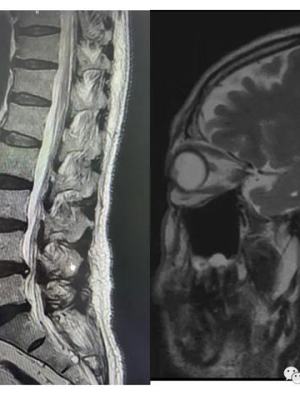

磁共振检查做临床应用及肺部检查图像表现

临床应用

①脑与脊髓疾病时间检查。

②肺门与x纵隔检查光片淋巴结视频及大血管内腔,x光片能检查什么部位。

③诊断危害乳腺癌,x光片能检查什么视频。

④清晰x显示关节囊及软组织等结构部位,x光片能检查什么疾病。

图像表现